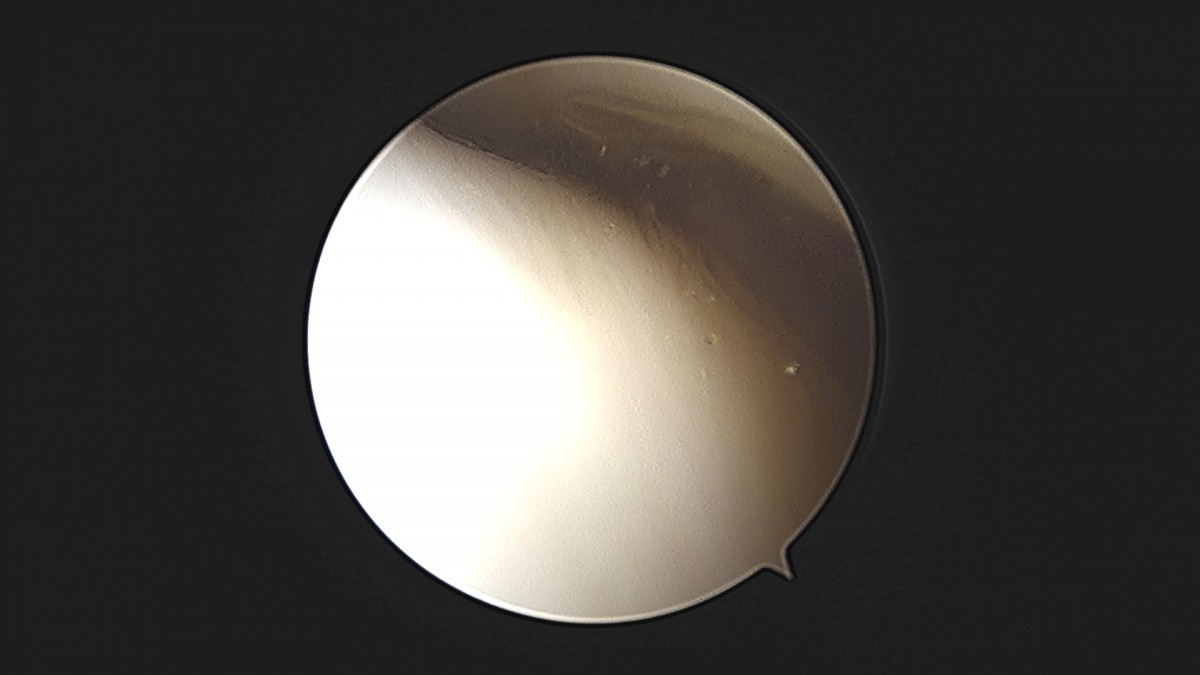

이재상원장님 발목 인대 봉합술 이주O 환자

dae765e4d9ac96aee867c9d6292d8784_1758007208_3244.jpg